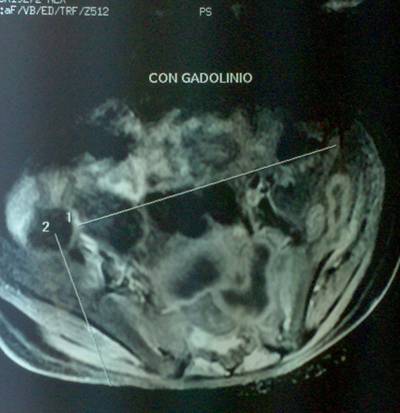

- Figura No 2a

- Figura No 2b

- Figura No 2c

- Figura No 2d

- Figura 2 Texto